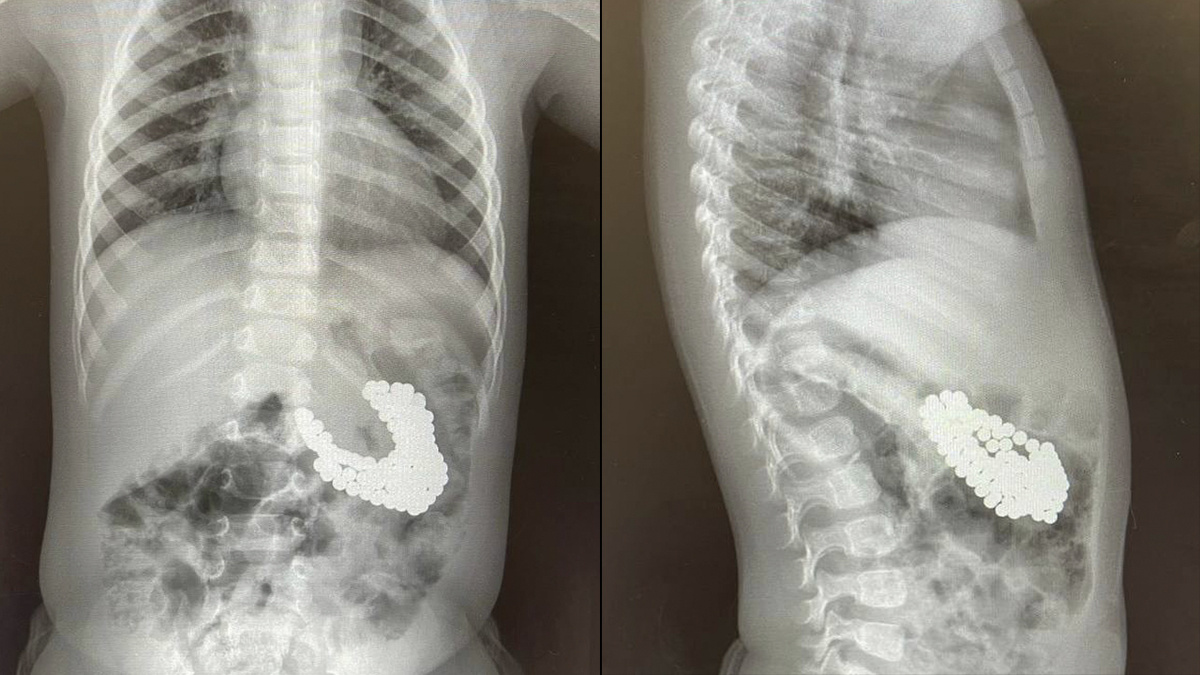

В Подмосковье малыш проглотил 130 магнитов и батарейку

Врачи Центра Рошаля спасли полуторагодовалого мальчика, проглотившего 130 магнитов и литиевую батарейку.

Родители малыша заподозрили, что он мог что-то проглотить, и вызвали медпомощь. Обследование показало, что в желудке у мальчика множество цветных магнитов, которые сцепились друг с другом, что привело к повреждению слизистой оболочки и образованию язвы. Извлечь инородные тела надо было как можно быстрее — чем дольше магниты и батарейки находятся в организме, тем больше вероятность ожогов, перфорации внутренних органов, некроза тканей и кровотечений.

«Действовать нужно было быстро. С помощью специальных инструментов - эндоскопического «Сачка», зажима по типу «Аллигатор» и «Корзины Дормиа» мы провели гастроскопию, в ходе которой последовательно извлекли инородные тела из желудка мальчика», — рассказал заведующий эндоскопическим отделением центра Александр Иноземцев.

После операции рентгенография показала еще три магнита, которые невозможно было удалить с помощью эндоскопа. Похоже, ребенок глотал магниты в разное время, поэтому некоторые из них уже переместились в кишечник. В организме магниты сцепились и притянули друг к другу желудок и кишечник.

Торакальные хирурги достали оставшиеся магниты через маленькие разрезы в брюшной стенке с помощью лапароскопа и телескопической трубки. Операция также прошла успешно, мальчик чувствует себя хорошо и уже выписан на амбулаторное лечение.